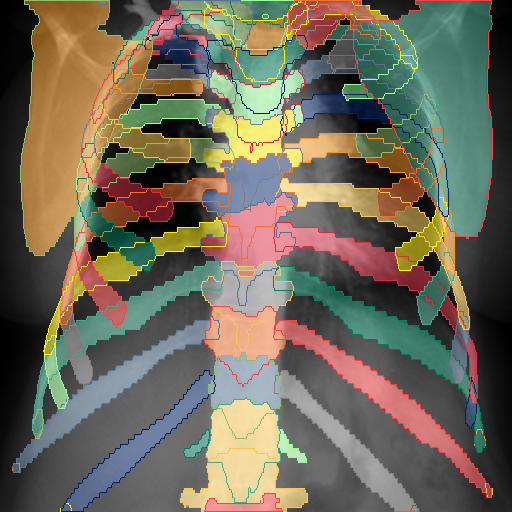

Furthermore, when projecting the pseudo-labels to a frontal or lateral view, we merge classes to accommodate the characteristics of the view. For example, distinguishing between the left and right scapula is impossible in the lateral view, whereas this is trivial in the frontal view. On the other hand, the subsegments of the lower mediastinum is better distinguishable in the lateral view, while not in the frontal one. We display the final classes in Fig. 6.

Class Center Distributions. In Figure 9, we show the center-point distributions for several superclasses denoted with a corresponding color. We note that the effect of the provided crop in the original datasets leads to a difference in the position and scale of the thoracic anatomy after rescaling the projections to a uniform size. The frontal ribs in green illustrate this, as the center points of the individual anterior and posterior rib parts contain a noticeable separation at the bottom half of the image. We observe that the individual classes belonging to bones (1st column, vertebrae in blue, clavicles and scapulae in orange, ribs in green), abdomen (4th column, purple), and the respiratory (2nd column, lung sections in blue, trachea orange) and cardiovascular (3rd column, shades of red) systems appear in the expected positions for a standard CXR in both frontal and lateral views.